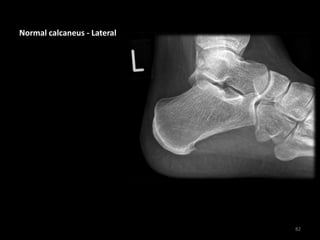

Normal calcaneus - Lateral

Bohler's angle is normal

(39° in this case)